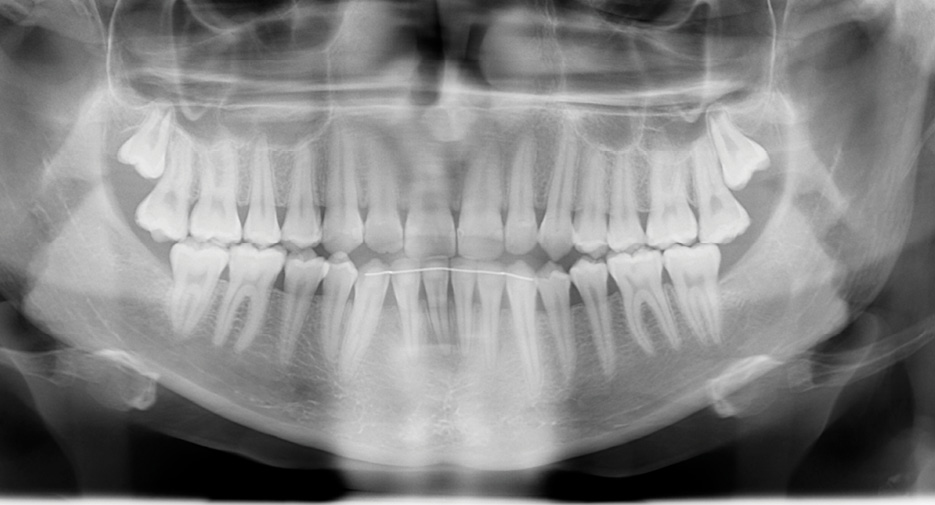

После проведения клинического обследования и антропометрии гипсовых моделей челюстей выявлено соотношение зубных рядов по III классу Энгля (мезиальная окклюзия) (рисунок 2), правильные форма и размеры зубных дуг верхней и нижней челюстей.

Рисунок 2. Смыкание зубных рядов (слева, спереди, справа), верхний и нижний зубные ряды пациентки Т., 18 лет, с мезиальной окклюзией гнатической формы до операции на нижней челюсти.

На ОПТГ наблюдается 30 постоянных зубов, отсутствуют зубы 3.8, 4.8. (рисунок 3). Анализ телерентгенограммы головы в боковой проекции (ТРГ) в программе Dolphin Imaging (США) (рисунок 4) показал: нормальные значения угла SNА = 81,2° (норма = 82°±2) и длины основания верхней челюсти (ANS-PNS) = 49,7 мм (норма = 51,6 мм); увеличение угла SNB = 87,1° (норма = 80°±2) и длины основания нижней челюсти (Pg-Go) = 85,7 мм (норма = 74,3 мм); отклонение и отрицательное значение угла ANB = -6 ° (норма = 1±1°); Wits-число равное -8.7 (в норме 1±1), что подтверждает наличие скелетной формы мезиальной окклюзии, обусловленной передним положением и макрогнатией нижней челюсти при нормогнатии и правильном положении верхней челюсти относительно переднего отрезка черепа. Это позволяет предположить наличие изменений в сосудах головы и шеи и гемодинамики в них. Для подтверждения диагноза была проведена ультразвуковая допплерография (триплексное сканирование) сосудов головы и шеи справа и слева (рисунок 5).

Рисунок 3. Ортопантомограмма пациентки Т., 18 лет, с мезиальной окклюзией гнатической формы до операции на нижней челюсти.